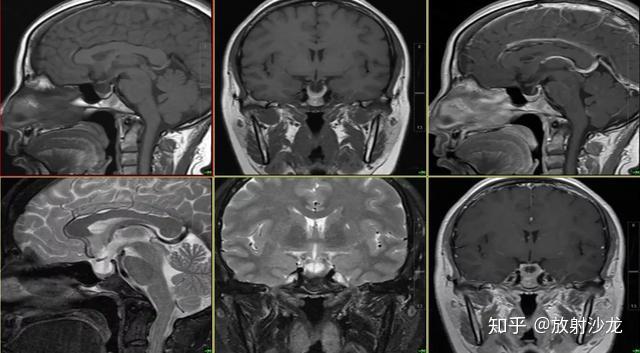

rathke囊肿轴位t2wi像(a),冠状位t2wi像(b)和矢状位t1wi像(c)显示垂体